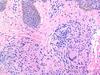

33

33. The pathology seen here is taken from a 68-year-old male with a diffuse skin eruption, with few blisters and crusting on the oral mucosa. Which of the followin is the most likely diagnosis? A. Lupus erythematosus (chronic or discoid) B. Pemphigus vulgaris C. Tumid lupus D. Porphyria cutanea tarda E. Bullous pemphigoid

Correct choice:B. Pemphigus vulgaris Explanation: The suprabasal acantholysis that extends down adnexal structures is most consistent with pemphigus vulgaris. Chronic discoid lupus and tumid lupus will have superficial and deep perivascular lymphoid infiltrates and dermal mucin.PCT will have a cell-poor subepidermal vesicle and thickening of superficial dermal blood vessels. Bullous pemphigoid will have a cell-rich subepidermal vesicle with eosinophils.